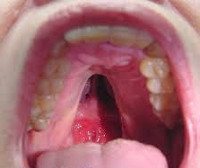

Проявления велокардиофациального синдрома можно обнаружить уже сразу при рождении ребенка, однако это не всегда позволяет сразу же поставить такой диагноз. Во-первых, это связано со схожестью проявлений заболевания с другими аналогичными синдромами (Ди Джорджи, Шпринтцена), во-вторых, часть симптомов начинает проявляться с возрастом и не регистрируется в младенчестве. Одним из наиболее явных проявлений велокардиофациального синдрома является характерный тип лица - выявляется отведение нижней челюсти назад, малый размер носа и рта, расширение переносицы. Могут наблюдаться деформации хрящей носа и ушных раковин. Расщелина твердого нёба присутствует у всех больных велокардиофациальным синдромом, но выраженность этого нарушения может быть различна - от резко явного до почти незаметного, выявляемого только при инструментальных исследованиях.

Диагностика велокардиофациального синдрома производится на основании данных настоящего статуса пациента, изучения сердечно-сосудистой, эндокринной и нервной систем, а также генетических исследований. При этом для подтверждения диагноза без участия врача-генетика может потребоваться несколько лет наблюдений, так как многие из симптомов неспецифичны, а некоторые проявляются только по достижении больными определенного возраста. При осмотре новорожденного выявляют расщелину нёба той или иной степени выраженности, иногда она сопровождается и расщеплением верхней губы. У больных велокардиофациальным синдромом также определяется характерный внешний вид - широкая переносица, выступающий нос, маленький рот, низкорослость. У младенцев довольно часто обнаруживается недобор массы тела, а в дальнейшем - отставание в физическом развитии от сверстников. При пальпации может определяться мышечный гипотонус, заторможенность рефлексов.

Специфического лечения велокардиофациального синдрома не существует, возможно только симптоматическое лечение и коррекция аномалий развития нёба, лица, сердечно-сосудистой системы. Самой частой паллиативной операцией при этом заболевании является коррекция расщелины твердого неба - нередко ее производят еще в младенческом возрасте, так как этот дефект значительно осложняет питание ребенка. Судороги, обусловленные гипокальциемией, устраняют назначением препаратов кальция - в большинстве случаев это позволяет полностью купировать данное проявление велокардиофациального синдрома. В ряде случаев необходима хирургическая коррекция аномалий сердца и сосудов, которая может производиться кардиохирургами в различном возрасте в зависимости от характера, выраженности и других обстоятельств.